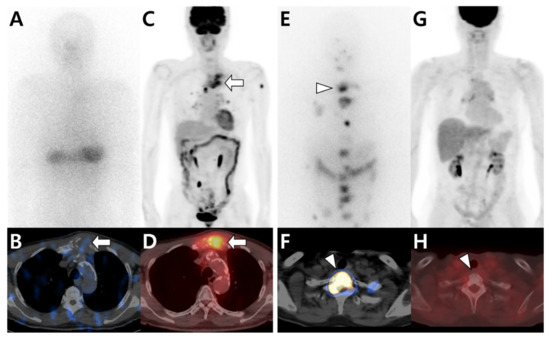

- Seo, H.J.; Choi, Y.J.; Kim, H.J.; Jeong, Y.H.; Cho, A.; Lee, J.H.; Yun, M.; Choi, H.J.; Lee, J.D.; Kang, W.J. Evaluation of Bone Metastasis from Hepatocellular Carcinoma Using (18)F-FDG PET/CT and (99m)Tc-HDP Bone Scintigraphy: Characteristics of Soft Tissue Formation. Nucl. Med. Mol. Imaging 2011, 45, 203–211. [Google Scholar] [CrossRef][Green Version]

- Ho, C.L.; Chen, S.; Cheng, T.K.; Leung, Y.L. PET/CT characteristics of isolated bone metastases in hepatocellular carcinoma. Radiology 2011, 258, 515–523. [Google Scholar] [CrossRef] [PubMed]

- Yoo, S.W.; Kim, D.Y.; Pyo, A.; Jeon, S.; Kim, J.; Kang, S.R.; Cho, S.G.; Lee, C.; Kim, G.J.; Song, H.C.; et al. Differences in diagnostic impact of dual-tracer PET/computed tomography according to the extrahepatic metastatic site in patients with hepatocellular carcinoma. Nucl. Med. Commun. 2021, 42, 685–693. [Google Scholar] [CrossRef] [PubMed]